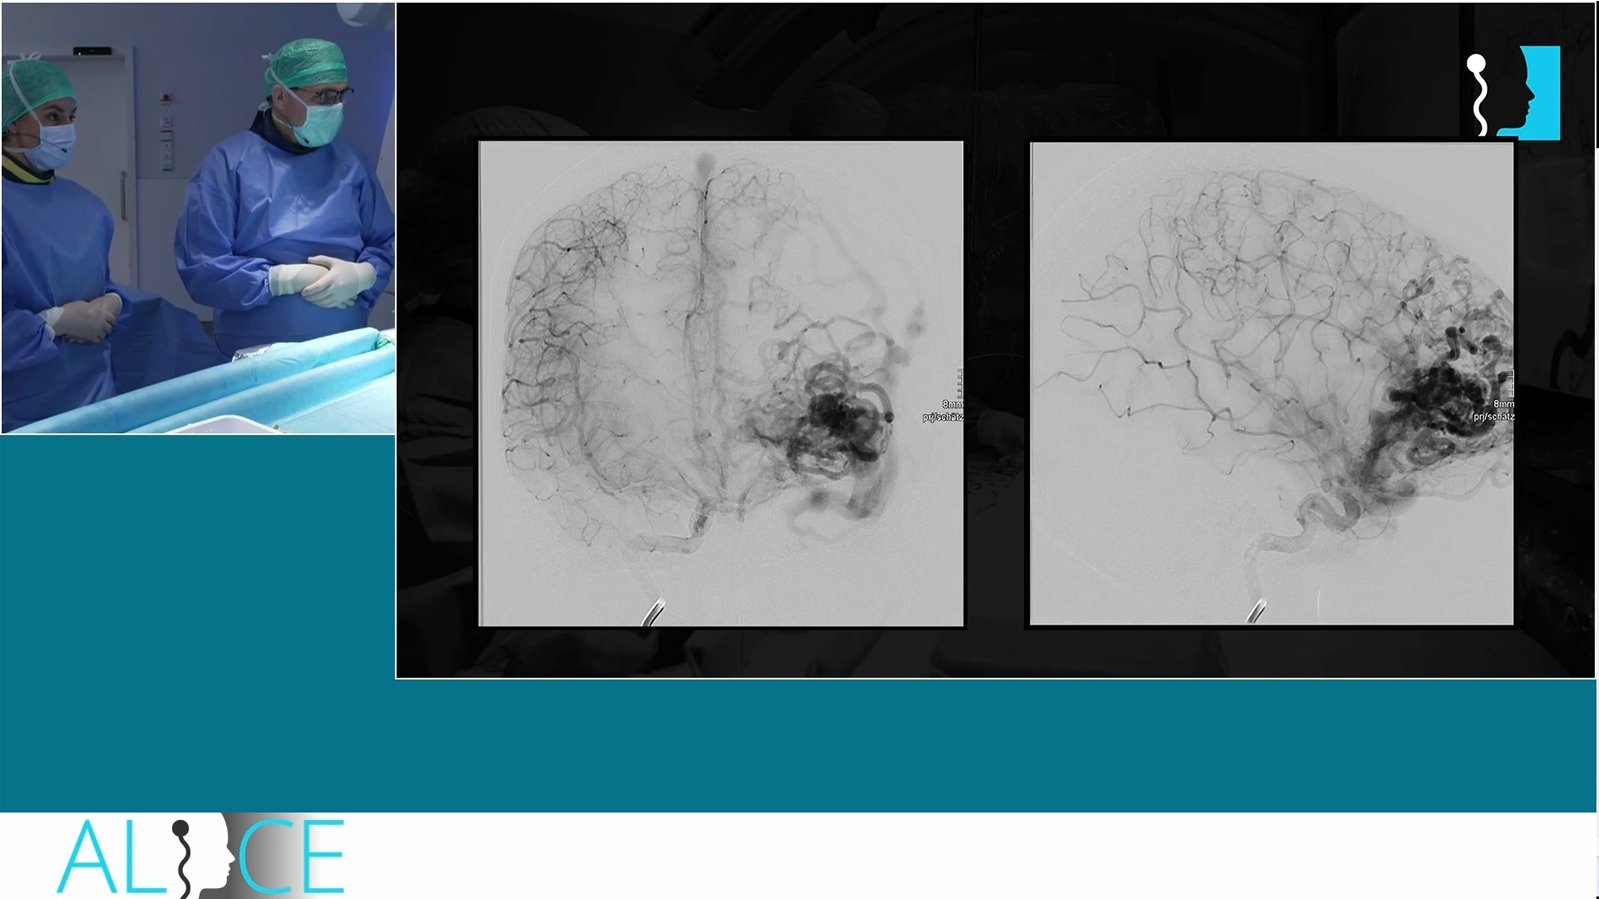

Occipital AVM treated by transarterial pressure cooker embolization

Temporal AVM treated by combined transarterial and transvenous embolization

Ruptured hypothalamic AVM treated by transarterial embolization with PHIL

Ruptured callosal AVM treated by transvenous pressure cooker embolization with onyx

Ruptured AVM with ventricular bleeding combined arterial and venous approach